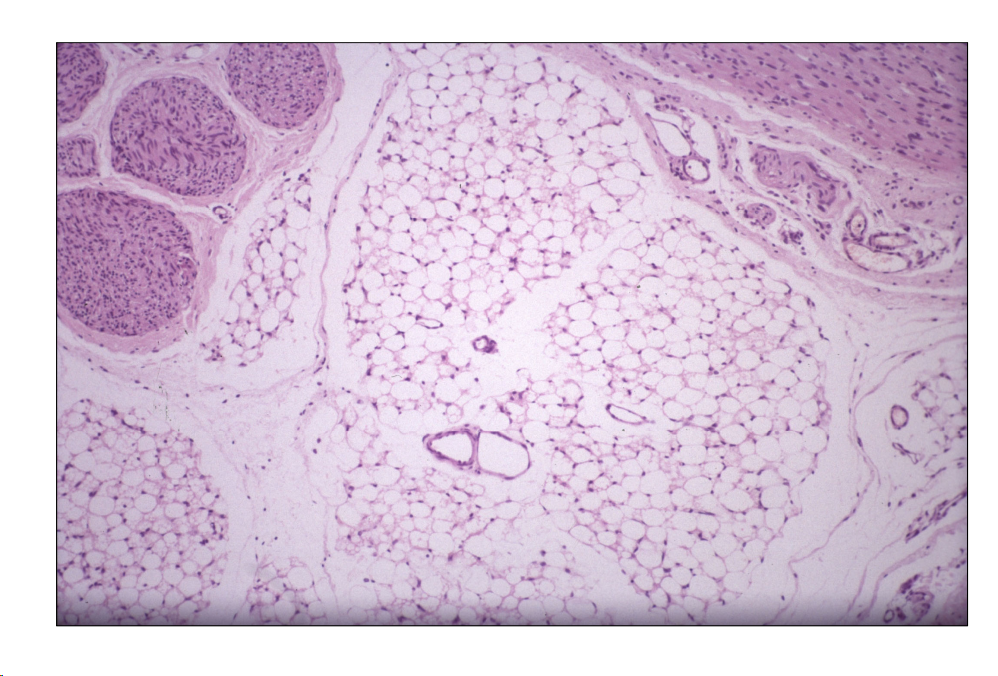

Aspecto microscópico:

Capilares y pequeños vasos distendidos y llenos de hematíes.

- Edema subcutáneo: aumento de tamaño, aspecto húmedo, gelatinoso.

- Microscopía: material eosinófilo homogéneo distendiendo tejidos, separación de fibras.